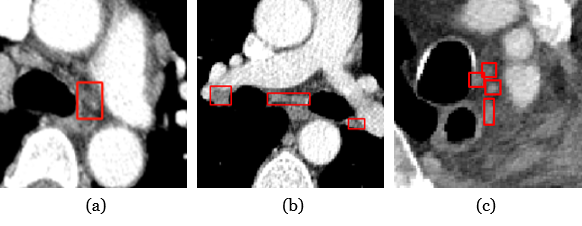

Accurate assessment of lymph node (LN) metastasis is crucial for the diagnosis and staging of cancer [1], and impact treatment planning and prognosis. Therefore, precise and automatic detection and quantification of lymph nodes from contrast-enhanced CT images is clinically imperative. However, accurately detecting lymph nodes on CT images poses several challenges. First, lymph nodes have lower contrast compared to surrounding tissues, making them difficult to be separated. While contrast CT can help differentiate vessels, identifying surrounding soft tissues remains difficult. Second, lymph nodes often exhibit irregular shapes and variable sizes, particularly in case of metastasis. They are also dispersed throughout the mediastinal area, rather than concentrated in a specific organ, making detection more challenging. Third, some abnormal lymph nodes may cluster together, further complicating accurate detection. Fig. 1 illustrates some typical examples of mediastinal lymph nodes.

Figure 1: Typical lymph nodes with annotated bounding boxes in contrast-enhanced CT images. (a) The lymph node exhibits low contrast with the surrounding tissues; (b) the lymph nodes have diverse size and shape; (c) the lymph nodes often clustered together.